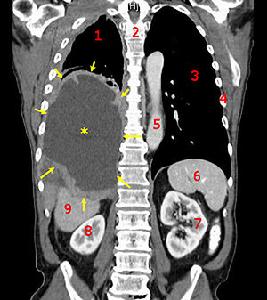

腹膜间皮瘤(图)

间皮瘤多发于胸膜和腹膜,是一种侵略性强的癌症。